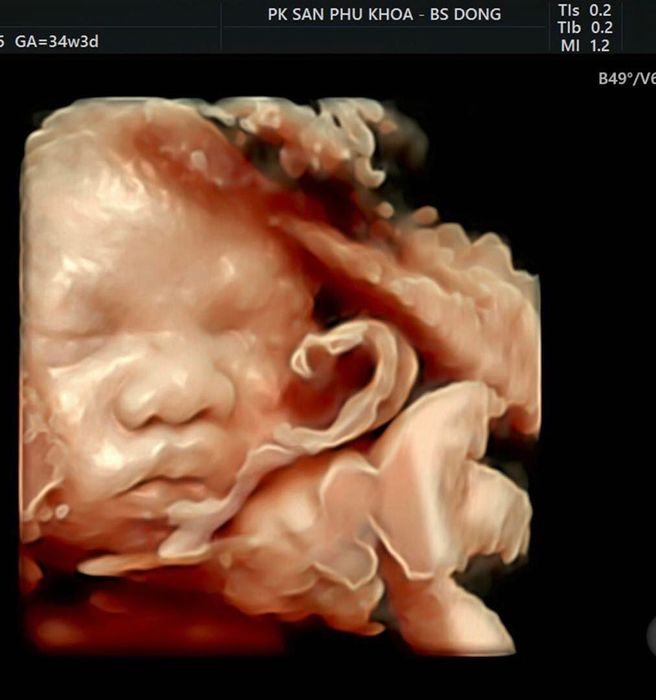

ThS. Bs. Kiều Văn Đồng trực tiếp điều hành phòng khám và theo dõi sát sao sức khỏe của mẹ và bé. Bác sĩ hiện đang là trưởng khoa sản tại Bệnh viện Bưu Điện với hơn 30 năm kinh nghiệm trong lĩnh vực sản phụ khoa. Bác sĩ Đồng nổi bật với chuyên môn trong các lĩnh vực đỡ đẻ, mổ lấy thai, điều trị u xơ tử cung, u nang buồng trứng và u xơ vú, luôn cam kết mang đến chất lượng dịch vụ tốt nhất cho mẹ và bé. Phòng khám không ngừng cập nhật các kỹ thuật mới như chẩn đoán dị tật trước sinh, sinh không đau, và tư vấn điều trị cho các cặp vợ chồng hiếm muộn.

Phòng khám bác sĩ Kiều Văn Đồng không chỉ khám thai mà còn điều trị tất cả các bệnh lý liên quan đến thai kỳ và cung cấp dịch vụ sinh đẻ cho các mẹ. Phòng khám cung cấp gói chăm sóc thai kỳ bao gồm khám thai, theo dõi định kỳ, tư vấn dinh dưỡng, tâm lý và chuẩn bị cho quá trình sinh nở. Đặc biệt, phòng khám còn cung cấp dịch vụ đặt lịch hẹn trước, giúp mẹ bầu tiết kiệm thời gian và tránh phải chờ đợi lâu.